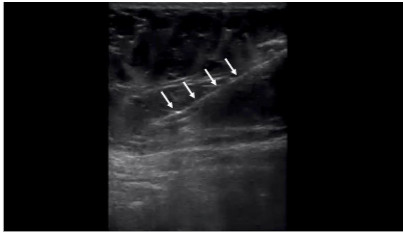

The layers of the abdomen can be evaluated from superficial to deep: the epidermis and dermis appear thin and hyperechoic; the adipose layer presents as hypoechoic and lobular with hyperechoic fibrous septa. Deep to the adipose layer, muscle appears relatively hypoechoic, separated by fine hyperechoic perimysium, while the bowel wall appears relatively hyperechoic with a hypoechoic lumen and is easily identified by its movement while the patient is at rest.

A “safe zone” for harvest can be defined as the area between the superficial apical layer and the deeper aponeurosis of the abdominal musculature in the upper abdomen, and Scarpa’s fascia in the lower abdomen. Depth markings on the ultrasound screen allow for measurement of the harvest field size. Dynamic scanning can help identify abdominal wall defects or hernias, while Color Doppler is used to locate vascular structures. A linear transducer provides superior resolution at shallow depths, whereas a curved transducer may be selected for larger body habitus or when a wider field of view is preferred. This approach enhances targeted harvest and reduces the risk of complications such as hematoma, seroma, or inadvertent injury to deeper structures.

The apical, mantle, and deep layers of the subcutaneous adipose compartment were distinguished, with the mantle and deep layers selected as preferred harvest targets due to their greater thickness. Depth markers on the ultrasound screen were used to measure adipose thickness and define the field size. Areas with potential umbilical hernias or fascial defects were identified and avoided. In clinical practice, Color Doppler can be employed to exclude vascular structures; however, it was not utilized in this cadaveric study.

Once the tumescent technique was complete, a 13-gauge blunt-tipped lipoaspiration cannula (Gallini Medical, Mantova, Italy) attached to a 20 mL VacLok syringe (Merit Medical Systems, Inc., South Jordan, UT) was inserted using an in-plane technique under real-time ultrasound visualization. The cannula was introduced at an angle of less than 30 degrees to the skin surface. Negative pressure was created by retracting and locking the syringe plunger. Gentle lateral-to-medial and medial-to-lateral sweeping motions were used following the pre-planned trajectories to aspirate adipose tissue while always maintaining visualization of the cannula on ultrasound. If cannula visualization was lost, the ultrasound transducer was moved to reacquire the image rather than moving the cannula blindly. Approximately 5 mL of adipose tissue was harvested bilaterally from the abdomens of three cadavers for a total of six 5 mL collections (30 mL in total). Once aspirated, the tissue samples were sent to a laboratory for analysis.